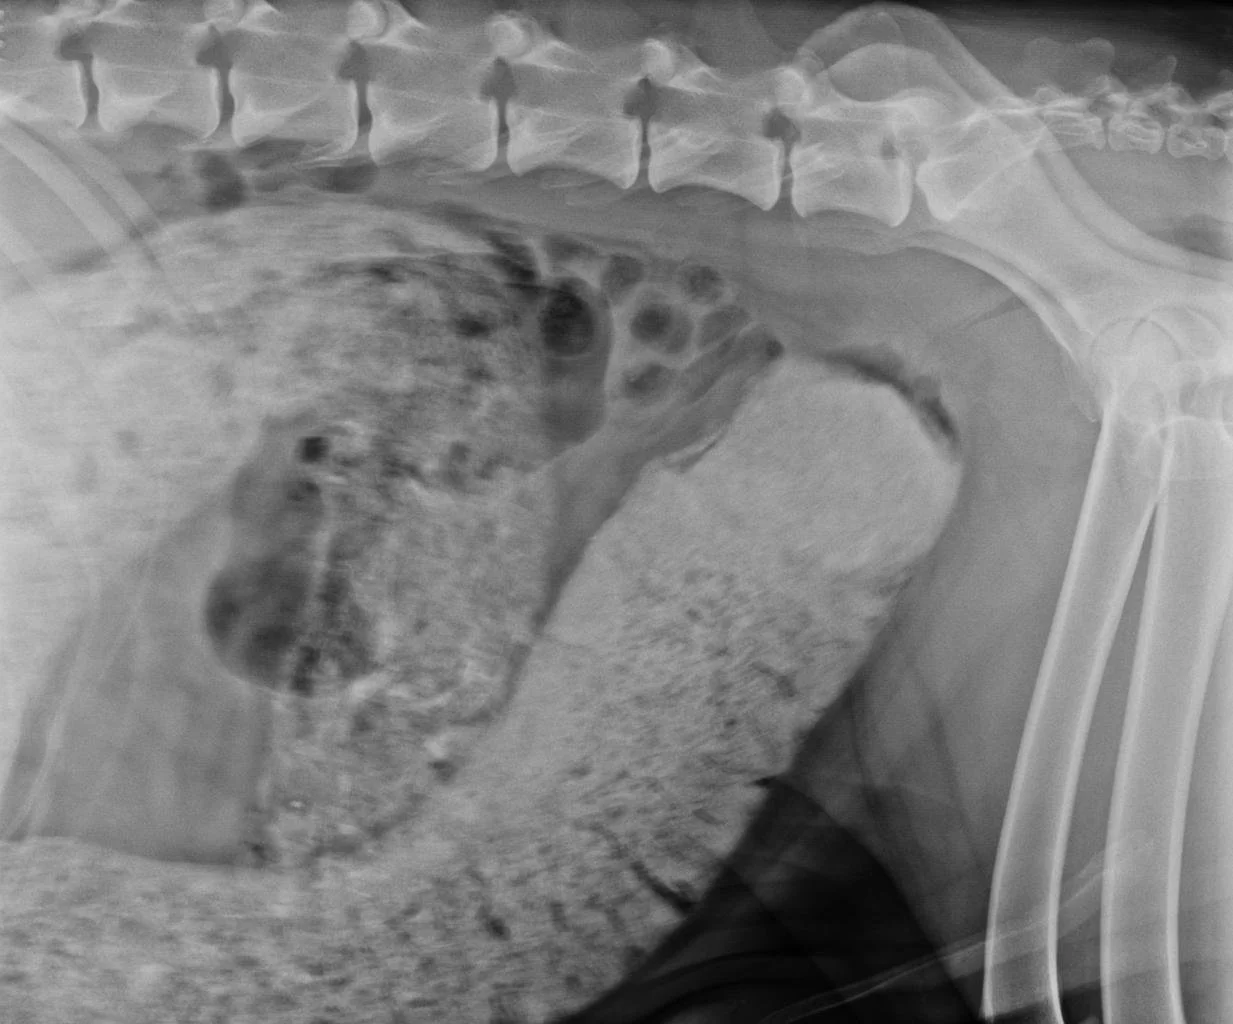

Intestinal Blockage in Dogs: Symptoms, Causes, and Treatment

Intestinal blockage in dogs is a dangerous condition that occurs when a swallowed object blocks the digestive tract. Learn the symptoms, causes, and treatment options.